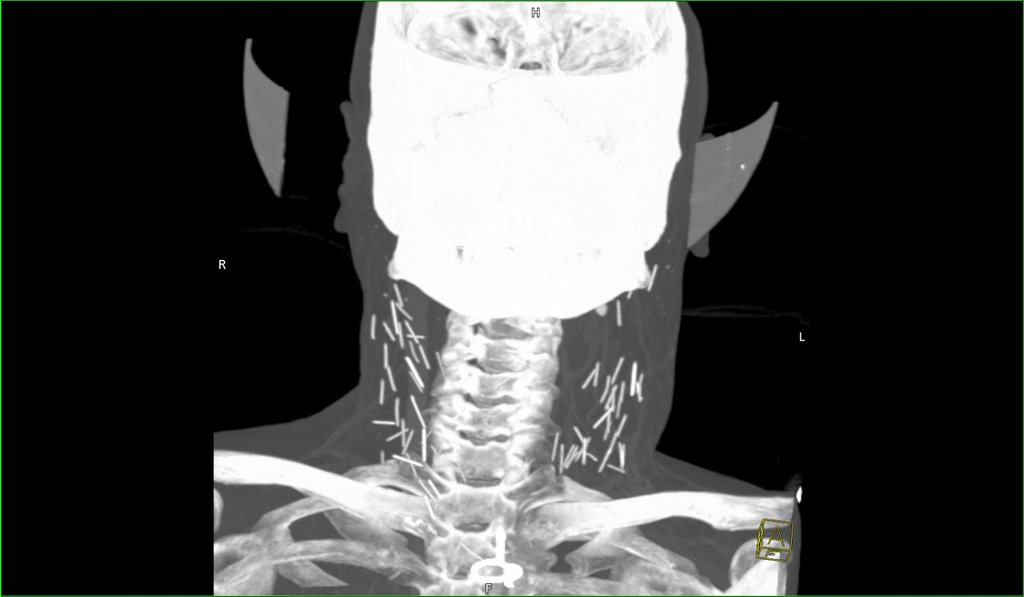

Deformutilation XRay Reveals Needles in the Neck Needle On Xray With the introduction of a newer and broader term “retained surgical items” (rsi), additional materials such as needles, broken instruments,. Imaging is especially necessary following the removal of multiple foreign body pieces or when wound exploration is not possible. On radiography, the needle appeared opaque ( fig. Of the more than 6 million who. Imaging modalities that can be. In. Needle On Xray.

Needles in neck Radiology Needle On Xray In many cases, these perforations do not occur acutely or cause acute symptoms. With the introduction of a newer and broader term “retained surgical items” (rsi), additional materials such as needles, broken instruments,. On sonography, the small diameter of the needle made it difficult to identify; Of the more than 6 million who. Imaging modalities that can be. On radiography,. Needle On Xray.

Deformutilation XRay Reveals Needles in the Neck Needle On Xray Metallic objects such as needles or elongated objects such as fish bones, chicken bones, and toothpicks are the foreign bodies most frequently reported to have caused a perforation (gharib et al., 2015). On radiography, the needle appeared opaque ( fig. If a sharp foreign body such as a needle enters the skin perpendicularly, the incision may miss the foreign body. Needle On Xray.